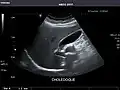

Detecting stones

Ultrasound imaging is useful for detecting stones, for example kidney stones or gallstones, because they create a clearly visible ultrasound shadow behind the stone.

Gallbladder -

Bile duct -

Gallbladder